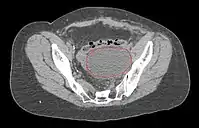

Lymphocele

- Seen postoperatively in up to 30% of GYN surgeries with pelvic/para-aortic LND

- Believed to arise from surgical transsection or inadequate ligation of draining lymphatics

- Lymphatic fluid may accumulate in various pelvic and retroperitoneal compartments

- Small lymphoceles typically resorb spontaneously

- Large lymphoceles may cause compression symptoms, and may result in abdominal distention, abdominal and pelvic pain, hydronephrosis, bladder dysfunction, constipation, tenesmus, edema of the ipsilateral leg and of the genitalia, and thromboembolism of iliac vessels

- Infection may cause fever, chills, and sepsis

- Symptomatic lymphoceles are typically managed initially with percutaneous CT-guided drainage, surgical therapy may be required

- Postoperative Lymphocele